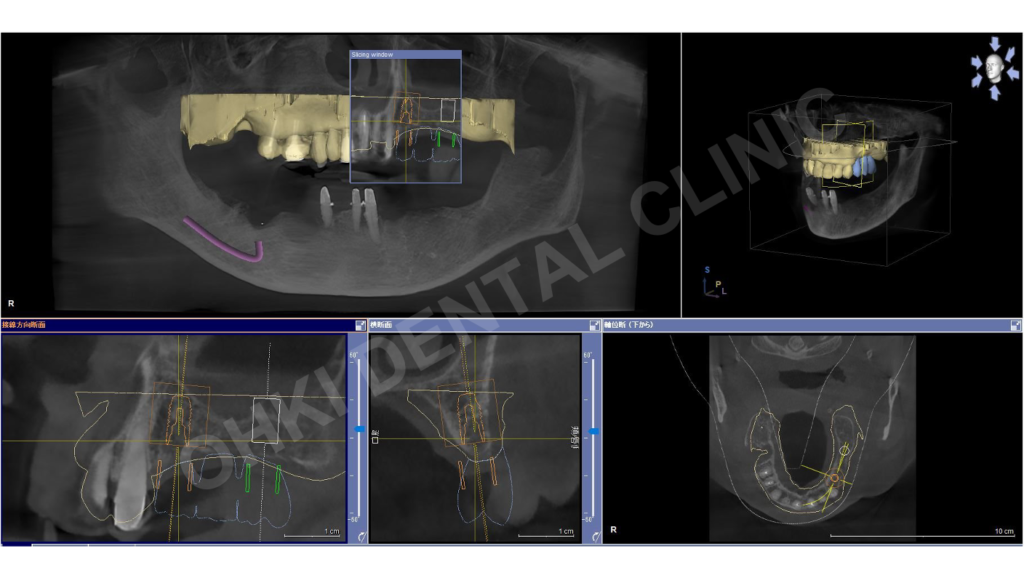

残すと決めた歯に対し、歯周ポケットを徹底的に除去する歯周フラップ手術を実施。 - インプラント手術:

左上臼歯部へのインプラント埋入。 - プロビジョナルレストレーション(多段階の仮歯):

歯周病の影響で移動してしまった歯に対し、「プロビジョナルレストレーション」を複数回作り直すことで、理想的な咬合平面と美しいスマイルラインを追求しました。 - 徹底したリスク除去:

インプラントと歯周病は非常に相性が悪いため、インプラント埋入前に残存歯の歯周外科処置を徹底し、口腔内の細菌リスクを最小限に抑えました。 - 効率的な治療計画: